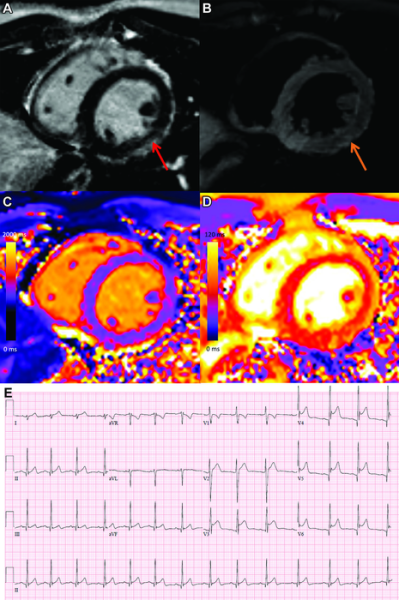

This photo gallery shows the variety of radiological presentations of COVID-19 (SARS-CoV-2) in medical imaging, including computed tomography (CT), radiograph X-rays, ultrasound, echocardiograms and magnetic resonance imaging (MRI). The radiology images show examples of typical COVID pneumonia in the lungs and the numerous complications the virus causes in the body in multiple organs, including the brain, kidneys, heart, abdomen and vascular system.

Ultrasound, especially hand-held ultrasound imaging devices, have become a primary imaging modality for novel coronavirus because of the ease to bag the device and sterilize it after use. CT and mobile X-ray systems are also used as front-line imaging systems for COVID-positive or suspected COVID patients.